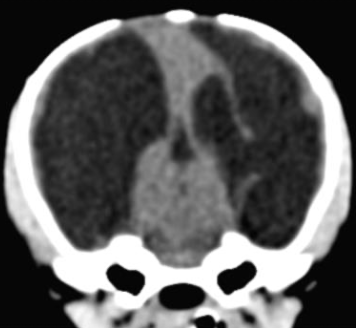

Figur 1. T2W dorsal MRI bild visar av en Fransk bulldog med en neoplastisk förändring, sannolikt ett gliom, i vänster frontallob.

Figur 2. Transversal DT bild av en ung chihuahua med grav hydrocefalus

Figur 3. T2W transversal MRI bild av en chihuahua med meningoencefalit av okänd etiologi (MUE)